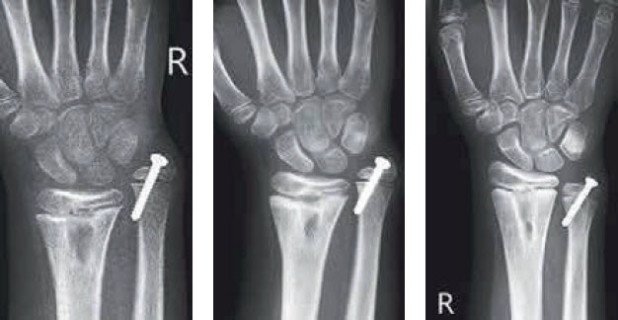

Ellenfuge

Die Ellenfuge wird temporär mit einer Schraube gebremst – die Radiusfuge wächst jetzt normal weiter

Wenn die Fugenbrücke dagegen nicht mehr entfernt werden kann, muss weiteres Fehlwachstum verhindert werden. Dazu wird die betroffene Wachstumsfuge komplett verschlossen, in der Regel mit einer Bohrung durch die Fuge, und die bereits vorhandene Fehlstellung mithilfe einer Umstellungsosteotomie korrigiert. Eventuell muss bei bleibender Verkürzung zusätzlich eine Knochenverlängerung mit externer Fixation durchgeführt werden.